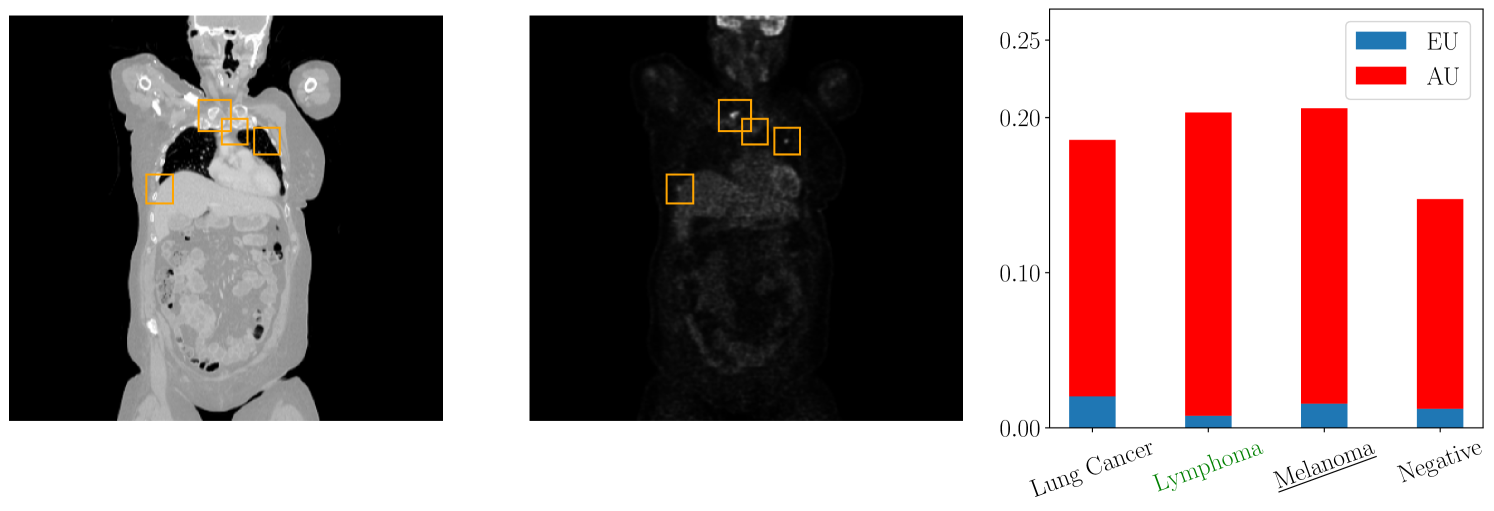

For the evaluation in the medical domain, we use a data set of Positron Emission Tomography/Computed Tomography (PET/CT) images which comprises 501 full-body scans from patients with malignant lymphoma, melanoma, and lung cancer, as well as 513 scans from individuals without malignant lesions (negative controls) [Gatidis et al., 2022]. Each scan is annotated with a tumor segmentation performed by a medical expert. We extract from each 3D CT and PET volume multiple 2D images which are used to train a deep neural network ensemble and evaluate the label-wise uncertainty quantification.

Figure 2 depicts a qualitative example of a 2D PET/CT image from the data set with the corresponding label-wise uncertainties from our evaluation. We observe low aleatoric uncertainty and negligible epistemic uncertainty for the melanoma class. This implies that the approximation of the aleatoric uncertainty is reliable. On the contrary, the classes lung cancer and lymphoma are associated with high aleatoric and high epistemic uncertainty, suggesting that the prediction with respect to these classes may not be accurate. This observation is plausible from a medical perspective as we observe multiple tumors in the image which are not limited to the lung area and thus might indicate a different tumor class as well. In this instance, we could request a medical expert to annotate additional data for the classes lung cancer and lymphoma, thereby diminishing the epistemic uncertainty associated with these classes. Here, a global measure of uncertainty would only give epistemic uncertainty with respect to all classes, meaning a doctor would have to annotate data for all classes.

Having a more detailed understanding of the label-wise uncertainties is crucial for the decision-making in medical applications supporting a given diagnosis. Moreover, it allocates resources to the relevant classes and saves valuable examination time and costs.